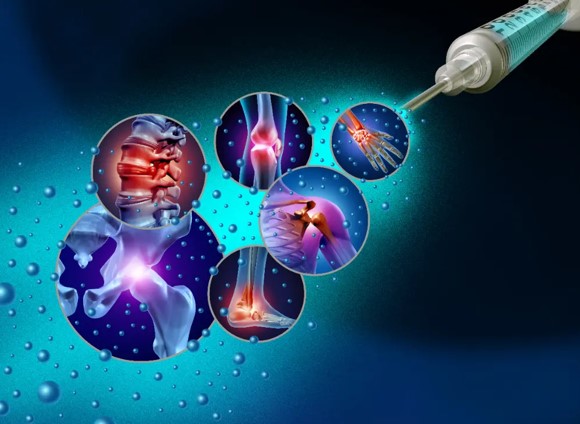

Advanced treatments using PRP, stem cells, and other biologics to stimulate natural healing.

Comprehensive care for athletes including injury prevention, treatment, and performance enhancement.

Minimally invasive procedures for joints using small incisions and specialized instruments.

Advanced techniques to manage arthritis and preserve natural joint function for as long as possible.